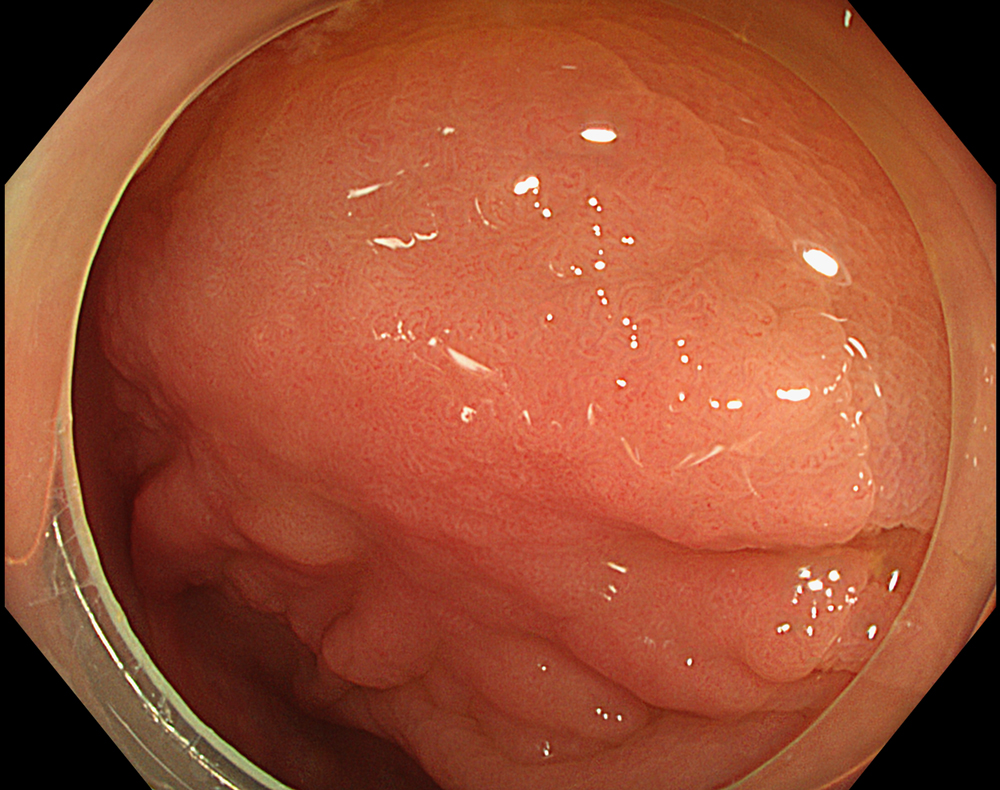

1. LST-NG in WLI

A 30-mm non-granular laterally spreading tumor (LST-NG-FE) located at the hepatic flexure is observed as a flat elevated lesion on white light imaging.

Enhancement : A8

NBI Mode : NA

TXI Mode : NA

RDI Mode : NA

BAI-MAC : On